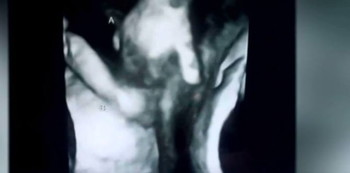

An incredible sonogram image shows the two fraternal twins holding hands. As if to let her twin brother know she’s there for him, we see her clutching his hand is they rest peacefully in their mother’s womb.

Due to a hold in his heart and an abnormal brain, chances for survival are slim. But Ian and Brittani McIntire of Hutchinson, Kansas take comfort in knowing that the twins will be there for one another.

They’ve named the twins Madilyn and Mason.